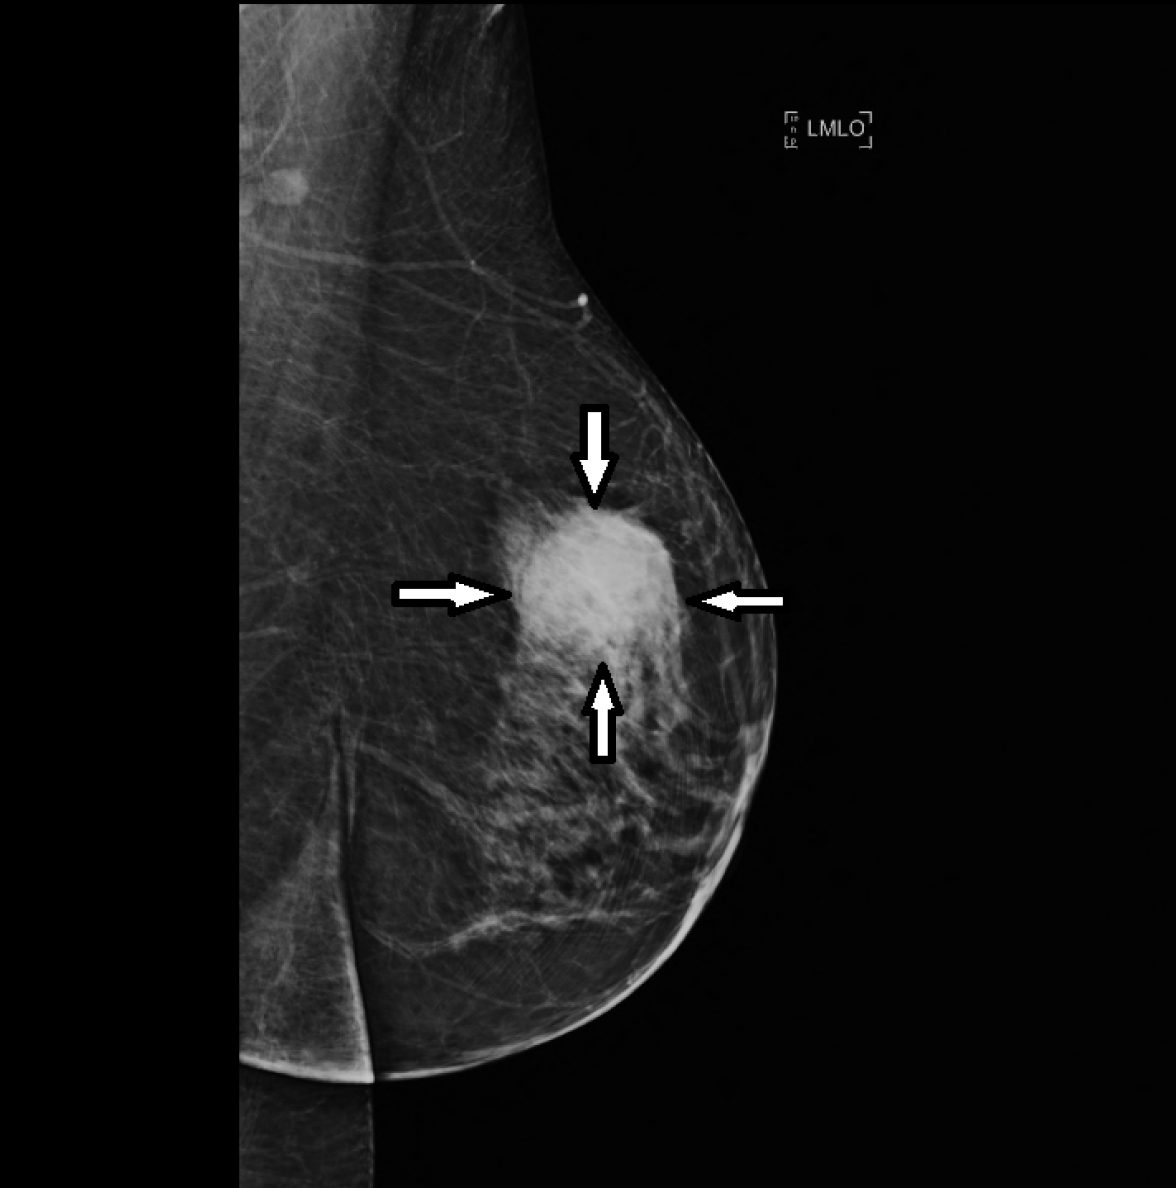

Examen de référence, la mammographie peut être réalisée dans le cadre d’un dépistage organisé ou bien suite à une anomalie retrouvée à l’examen clinique. La mammographie est un examen pratiqué et interprété par un radiologue. C’est la classification ACR (Classification BI-RADS de l’American College of Radiology) qui est utilisée pour l’interprétation des clichés de mammographie (ACR0 jusqu’à ACR 5).

Devant la découverte d’une anomalie à la mammographie, une biopsie mammaire est indiquée.

Il existe deux types de biopsies mammaires et le choix de fait en fonction de l’anomalie retrouvée: la microbiopsie et la macrobiopsie. La biopsie mammaire est un geste de radiologie interventionnelle réalisé par un médecin radiologue. Elle peut être échoguidée, guidée par mammographie (on parle de guidage stéréotaxique) ou bien plus rarement guidée par IRM.